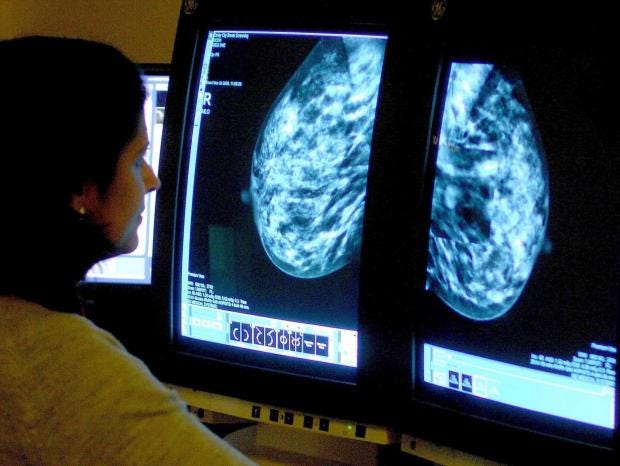

Breast cancer treatment 'holy grail' within reach after breakthrough, scientists claim

Scientists believe they may have found a way to create the “holy grail” of breast cancer research after an existing drug appeared to delay or even prevent tumours from forming in women with a particularly high risk of the disease.

“Early detection in order to improve breast cancer outcome and survival remains the cornerstone of breast cancer control,” the WHO says.